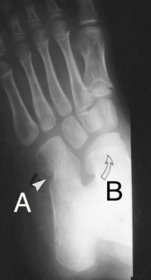

What is this? What is shown by A and B? | STJ coalition A = talar neck spurring B = Halo or 'C' sign |